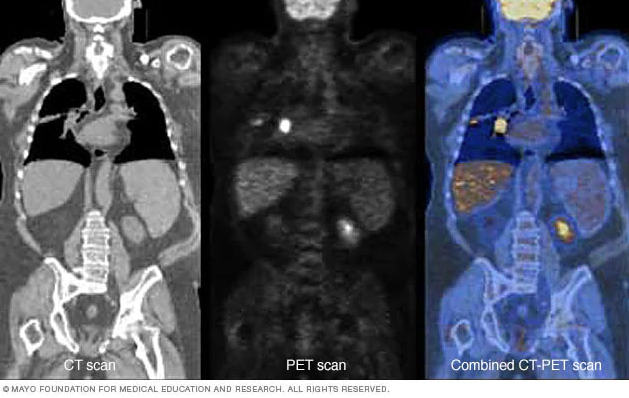

Напрямки науково-практичної роботи:

• розробка та модифікація методів променевої діагностики;

• вивчення ефективності методів ранньої променевої діагностики злоякісних новоутворень та визначення поширеності патологічного процесу;

• розробка радіологічних критеріїв ефективності лікування онкологічних захворювань та співставлення результатів променевих та морфологічних досліджень;

• розробка алгоритмів та стандартів променевої діагностики онкологічних захворювань різних органів та систем та їх впровадження в роботу лікувально-профілактичних закладів України;

• комплексна променева діагностика злоякісних новоутворень у дітей;

• комплексна променева діагностика злоякісних новоутворень легень та середостіння;

• радіологічні критерії ефективності лікування злоякісних лімфом, злоякісних новоутворень опорно-рухового апарату;

• комплексна променева діагностика та визначення поширеності злоякісних лімфом;

• комплексна променева діагностика раку тіла та шийки матки, трофобластичної хвороби;

• комплексна променева діагностика злоякісних новоутворень травного тракту;

• комплексна променева діагностика раку молочної залози.